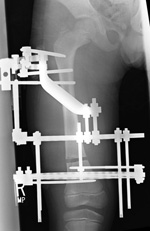

External lengthening. In this procedure, the doctor cuts the bone in the shorter leg into two segments, then surgically applies an "external fixator" to the leg. The external fixator is a scaffold-like frame that is connected to the bone with wires, pins, or both.

The lengthening process begins approximately 5 to 10 days after surgery and is performed manually. The patient or a family member turns the dial on the fixator several times each day.

When the bones are gradually pulled apart (distracted), new bone will grow in the space created. Muscles, skin and other soft tissues will adapt as the limb slowly lengthens.

The bone may lengthen 1 mm per day, or approximately 1 inch per month.

The external fixator is worn until the bone is strong enough to support the patient safely. This usually takes about three months for each inch of growth. Factors such as age, health, smoking and participation in rehabilitation can affect the amount of time needed.

X-ray shows lengthening of a child's femur using an external fixator.